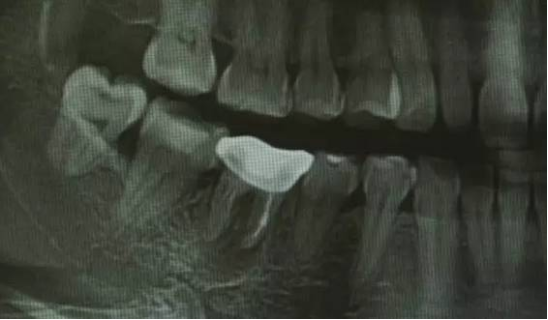

牙周脓肿与牙槽脓肿怎样区分?